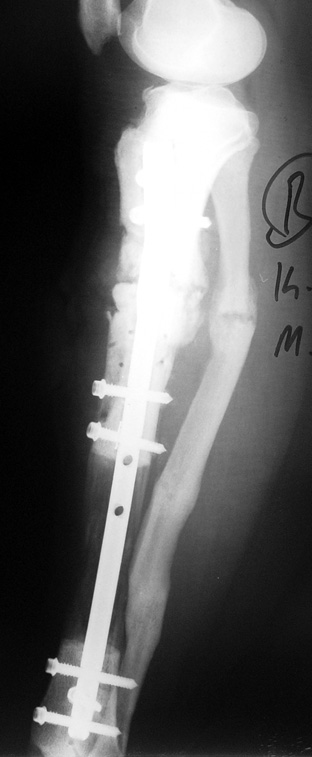

The duration of external fixation (external fixation index) depends on the amount of distraction required, and the extremity is prone to complications during this period. After the distraction phase is completed, the external fixator remains in place during the consolidation phase, which lasts twice as long as the distraction phase; but this period is hardly tolerated. If the external fixator is removed before sufficient consolidation is achieved, fractures, deformity and shortness will be the result. In our department, ‘lenghthening over nail’ method is used in order to decrease the external fixation index and increase patient comfort and activity level. In this method, the intramedullary nail is statically locked after the completion of the distraction phase, and external fixator is removed. The extremity is stabilized by the intramedullary nail during consolidation phase. In this way, complications due to long external fixation index or early removal of the external fixator are avoided.

Case 2